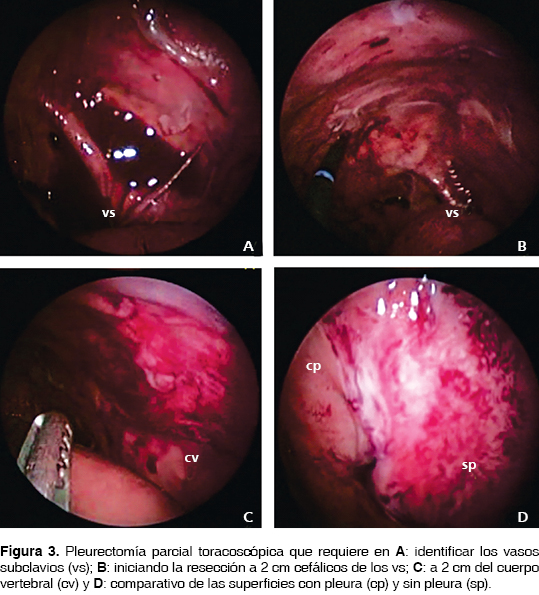

La actividad lúpica fue tratada prontamente con metilprednisolona en altas dosis, gama globulina intravenosa y rituximab sin mejoría alguna; fueron corregidos estados trasudativos de hipoalbuminemia, sobrecarga hídrica e hiponatremia. Bajo este panorama es considerado derrame pleural masivo, bilateral y refractario a manejo conservador, se realiza tratamiento quirúrgico con drenaje pleural y adherensiolisis del pulmón izquierdo atrapado con toma de biopsia pleural y pleurectomía parcial con pleurodesis química con yodo povidona al 1% por toracoscopia videoasistida. Del hemitórax derecho, una vez descartado por toracoscopia la presencia de un pulmón atrapado y confirmando la expansión pulmonar, se decidió instilar bajo visión pleurodesis química con yodo povidona al 1% y pinzamiento por cuatro horas de la sonda pleural (figuras 2 y 3). Se instiló vía intrapleural por tubo de toracostomía derecha y una sesión más con yodo povidona sin complicaciones. Con evolución satisfactoria fueron retirados los drenajes pleurales al tercer y cuarto día y documentadas la expansión pulmonar clínica y radiológica; y sin recurrencias a dos años de vigilancia y tratamiento médico inmunosupresor. El reporte histopatológico documentó pleuritis aguda y crónica inespecífica mayormente acentuado alrededor de los vasos sanguíneos, con hiperplasia mesotelial e infiltrado linfoplasmocitario. La citología del líquido pleural mostró células mesoteliales reactivas mezcladas con linfocitos.

Sin embargo, en nuestro paciente, la inserción de un catéter bajo guía metálica en el interior del espacio pleural permitió confirmar los beneficios terapéuticos del drenaje pleural con mejoría clínica de la disnea, y con mínimo riesgo de contaminación por comportarse como un sistema de drenaje cerrado estéril, al mismo tiempo que evita las toracocentesis repetidas.25-27 Más aún, ante la posibilidad de un derrame pleural tuberculoso, el drenaje pleural percutáneo favorece la evacuación segura y controlada del líquido pleural con bajo riesgo de engrosamiento pleural y la consecuente fístula pleurocutánea descrita en los derrames tuberculosos tratados con sonda pleural de toracostomía. El drenaje pleural y la pleurodesis por instilación de agentes esclerosantes como el talco libre de asbestos han mostrado éxito del 80 al 100% en el tratamiento de los derrames pleurales malignos recurrentes, comparado con la utilidad de la tetraciclina útil sólo en el 75% de los casos.24,28,29 Estas opciones de pleurodesis química pueden resultar en adherencias pleuropulmonares en parches, loculaciones y pulmón atrapado al ser realizados como procedimiento ciego por el tubo de toracostomía. Sin embargo, la incidencia reportada de síndrome de dificultad respiratoria, fiebre y el dolor torácico asociada a la instilación de agentes esclerosantes ha dirigido la atención a métodos combinados de tratamiento con pleurodesis local de yodo povidona (solución al 10%) instilados bajo visión asistida por toracoscopia, donde se adicionan la terapéutica segura y definitiva de la pleurectomía parcial o total, así como el diagnóstico definitivo de la biopsia pleural.30-33

En nuestro caso, las instilaciones repetidas con yodo povidona intrapleural por sonda de toracostomía son posibles en el seguimiento posquirúrgico y aseguran la efectividad reportada del 64 al 96%.34-36 La toracoscopia permite la evacuación y adherensiolisis del espacio pleural y confirma una completa expansión pulmonar, requisito indispensable para ejecutar la pleurodesis química. En pacientes con un síndrome de pulmón atrapado, la decorticación por toracoscopia con pleurectomía parietal representa el procedimiento de elección.24,31,37,38 El síndrome de pulmón atrapado con dificultades para ser resuelto por toracoscopia debe ser tratado con procedimiento abierto para decorticación y pleurectomía total, pleurodesis química adicional y considerar una derivación pleuroperitoneal.37-40